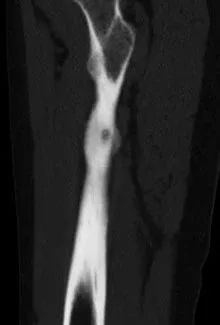

此为横切面图

陈先生左腿股骨病灶

术中,射频针直击病灶